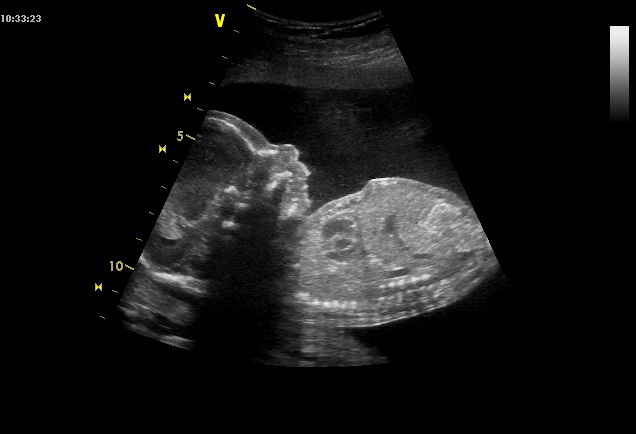

Ultrazvuk ve 20. tt - můžete se mrknout na fotku?

Ahoj všem. Minulý týden jsem byla na ultrazvuku ve 20. tt, vše bylo podle slov pana doktora v pořádku, dokonce mám i nějaké fotky. Můžete se prosím podívat na přiložený obrázek, má na bříšku nějakou bouli a já pořád zkoumám, co to může být. Třeba je to jenom, že se pohnul a mázlo se to nebo nevim. Předpokládám, že kdyby to byla nějaká anomálii, tak by mi to řekl, doktor je velice pečlivý. Ale pořád mi to vrtá hlavou, tak co myslíte? Jestli mi napíšete, že jsem bláznivá těhule, tak se zlobit nebudu